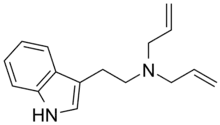

| DALT | artificial | H | H2C=CH-CH2 | H2C=CH-CH2 | N,N-diallyltryptamine | 60676-77-9 |